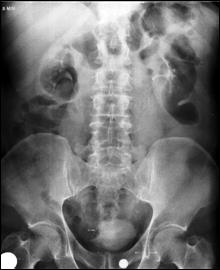

4.1. Radiografia renovezicala simpla si UIV raman examenele de baza pentru diagnosticul etiologic al oricarui pacient cu hematurie. Tumorile vezicale au drept semn radiologic cardinal imaginea lacunara pe cistograma urografica. Tumorile infiltrative pot induce modificari ale supletii peretelui vezical, care devine rigid, inextensibil, retractat etc. in zonele patologice. Ureterohidronefroza sau rinichiul mut sunt rezultatele invaziei si obstructiei ureterelor intramurale induse de tumorile solide, infiltrative (Fig.27,28,29).

Figura 28. Imagine

lacunara de 2,8/2 cm, in aria vezicii urinare, sugerand tumora

vezicala.